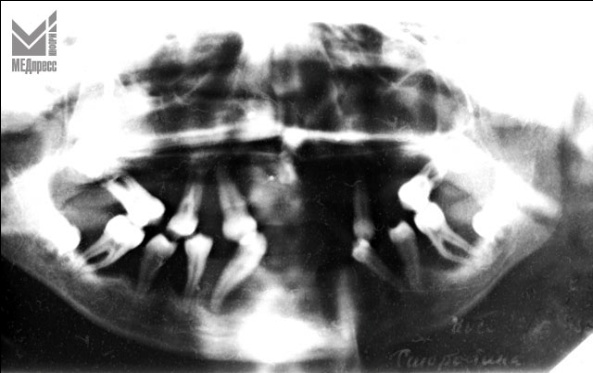

| Рис. 3. Остеолизис альвеолярного отростка лакунарного типа. |